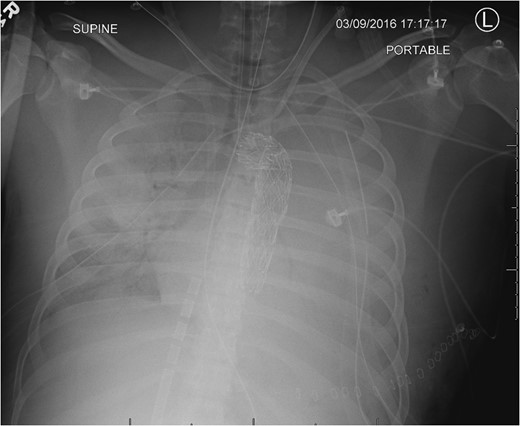

Admission AP CXR demonstrating a widened mediastinum and increased haziness of the left hemi-thorax.

A 21-year-old male involved in a motorcycle crash presented with abdominal hemorrhage and a widened mediastinum on chest radiograph. He required an initial exploratory laparotomy for mesenteric injuries. An aortic injury was confirmed on computed tomography imaging and he subsequently underwent attempted endovascular repair. During that procedure, the patient experienced massive thoracic hemorrhage with cardiac arrest and profound respiratory failure. Damage-control thoracic surgery and rescue extracorporeal membrane oxygenation were successfully utilized with a favorable outcome.